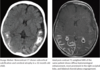

- Characteristic imaging findings are cortical atrophy and subcortical parenchymal calcifications, which are best seen on CT. Contrast-enhanced MRI demonstrates pial enhancement in regions affected by the leptomeningeal venous angiomatosis. The choroid plexi are typically enlarged from compensatory hypertrophy thought to be related to increased flow.